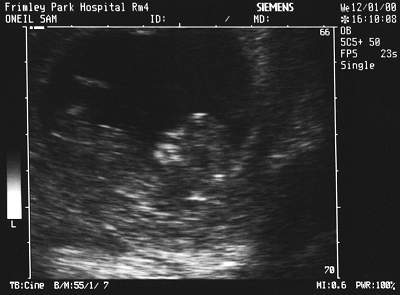

July 21 2000 10.30am- Simon, sitting next to Becky in the open incubator, notices shaking down the left hand leg and arm, as well as her eyes rolled round and upward. During the minute and a half it lasts, the SHO (Senior House Officer) doctor comes over and says that its a fit and arranges for a lumber puncture (to test for Meningitis amongst other things) and an ultrasound scan on the brain.

12 Jan 2000 - First Scan (12 weeks). The hospital have a policy of not telling you the sex, so as long as its a boy, I don't mind. Obviously Sam would like a girl!